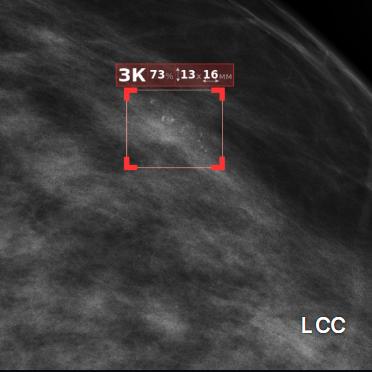

Система Цельс выделила подозрительную на злокачественное новообразование зону, чётко обозначив её красной «рамкой». Был определён размер патологического участка (менее 5 мм), рассчитана вероятность рака в процентах, и, что является ключевым, выставлена категория BIRADS 4 – это означает высокую подозрительность на злокачественный процесс и прямое показание к инвазивной диагностике (биопсии). Примечательно, что ИИ выявил патологию именно на снимке 2024 года, который ранее был классифицирован как «норма».

Возникшее расхождение между заключением ИИ и первоначальным описанием потребовало немедленного внимания. К анализу был привлечён эксперт мультимодальной диагностики молочных желёз Маммологического центра Л7, обладающий глубоким опытом и обширной «насмотренностью». После детального анализа маммограмм пациентки эксперт подтвердил наличие крайне малой опухоли. Дополнительный прицельный снимок выявил 7-8 кальцинатов на участке протяженностью 6х4 мм.